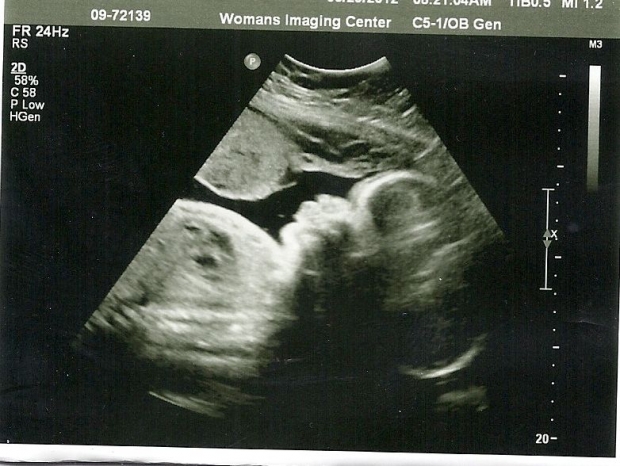

Плод достиг размера, сопоставимого с кулаком взрослого человека. На ультразвуковом исследовании, проведенном на 14-й неделе беременности, можно заметить, что все внутренние органы плода заняли свои окончательные позиции в брюшной полости, и больше не наблюдается выпячивания, как это происходило несколько недель назад. УЗИ уже позволяет различить даже узоры на ладошках малыша. Лицо начинает приобретать более четкие контуры, а длина шеи увеличивается. Плод активно сосет свои пальцы, что свидетельствует о развитии естественного рефлекса.